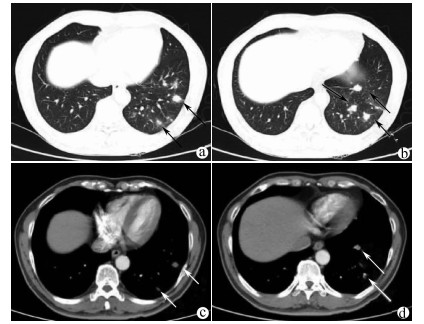

Complete remission after comprehensive treatment of lung metastases following liver cancer surgery: A case report